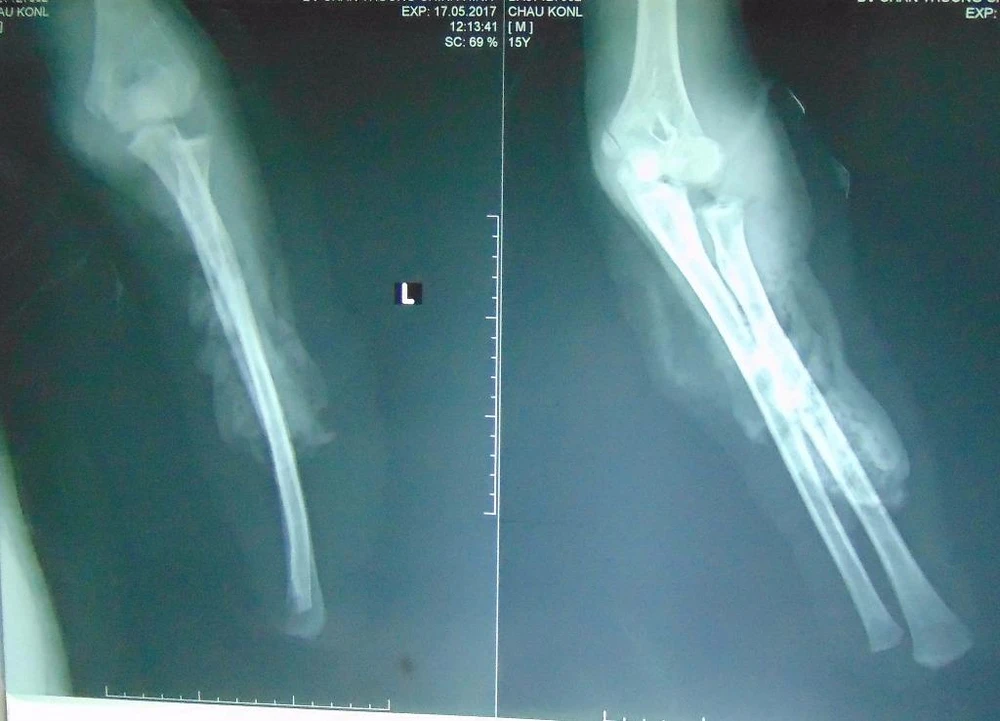

Tay trái bệnh nhân CK bị cắt cụt.

Tay trái bệnh nhân CK bị cắt cụt. Ảnh: TRẦN NGỌC

Do không thể nối lại tay đứt lìa nên các bác sĩ phải cắt đứt đến 1/3 trên cánh tay trái. Trong quá trình phẫu thuật, CK được truyền bốn đơn vị máu.